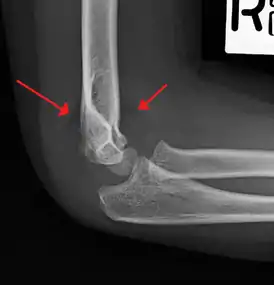

Fat pad sign/sail sign - A non-displaced fracture can be difficult to identify and a fracture line may not be visible on the X-rays. However, the presence of a joint effusion is helpful in identifying a non-displaced fracture. Bleeding from the fracture expands the joint capsule and is visualized on the lateral view as a darker area anteriorly and posteriorly, and is known as the sail sign.[7]

Anterior and posterior sail sign in a child who has a subtle supracondylar fracture